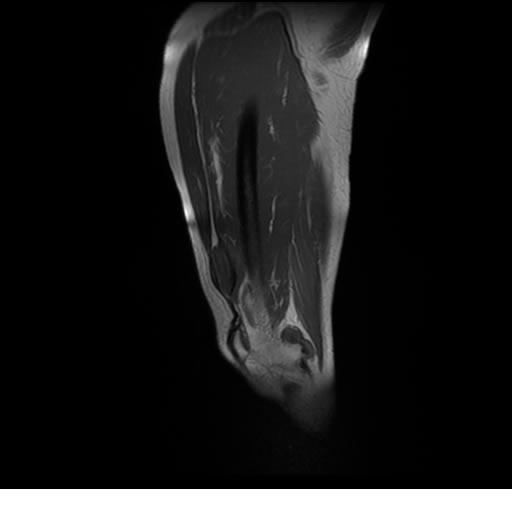

Se realiza estudio de MRI de pierna izquierda, utilizando secuencias Spin Echo y GRE en diferentes planos, se realiza angio MRI en fase arterial y venosa de pierna izquierda

HALLAZGOS IMAGENOLOGICOS

El estudio demuestra masa a nivel de los músculos gemelos, más evidente en secuencia con pulso de saturación de grasa, en el estudio de angio resonancia de pierna la fase arterial no muestra ninguna anormalidad, en la fase venosa se observa acumulo del medio de contraste a este nivel.

Se concluye que se observa una masa de tejido muscular sumamente vascularizada compatible con un hemangioarcoma.